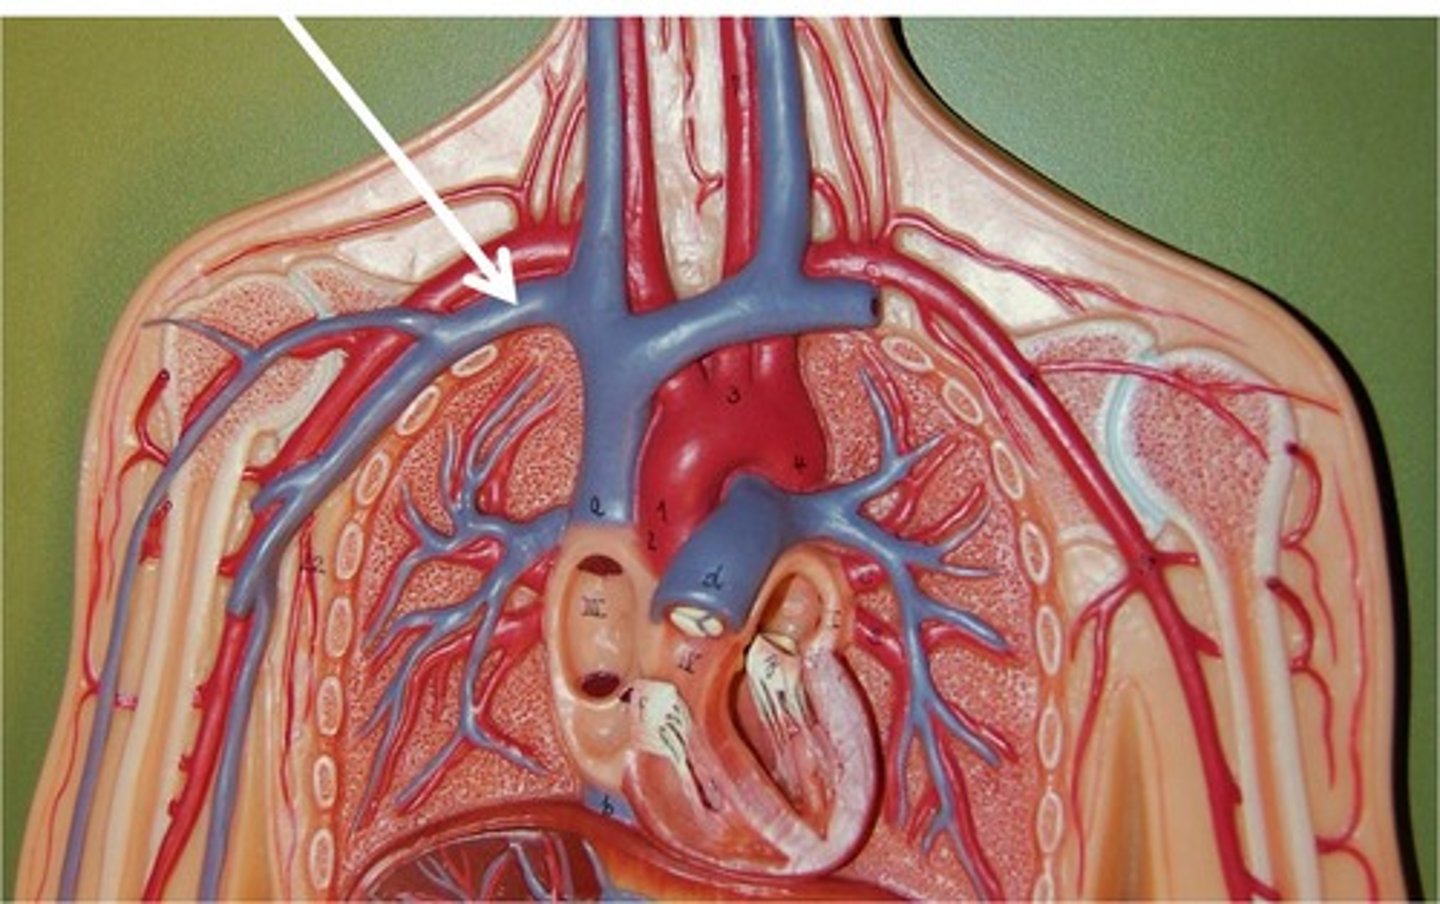

Thoracic duct (left lymphatic duct)

Subclavian vein

Pulmonary arteries

Pulmonary veins

Pulmonary trunk